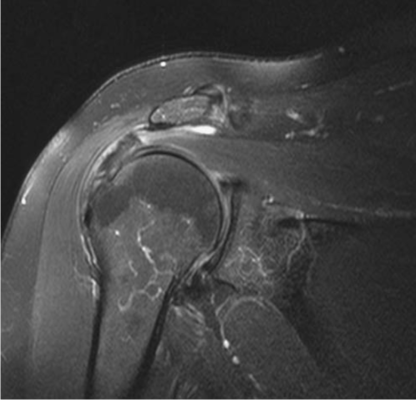

Chụp cộng hưởng từ (MRI):

Dành cho nghi ngờ rách CCX và không cải thiện triệu chứng dù điều trị đầy đủ 3-6 tuần. MRI có thể phát hiện nhiều tổn thương CCX từ thoái hoá đến rách hoàn toàn. MRI là phương pháp chẩn đoán hình ảnh tốt hơn nhiều phương pháp khác, đặc biệt là rách một phần. Nó có thể phát hiện rách trong gân hoặc rách gân mặt bao hoạt dịch, mà những phương pháp khác khó phát hiện. MRI cũng có thể ghi nhận những tổn thương mô mềm khác như cơ, dây chằng, bao khớp, sụn khớp, tuỷ xương.